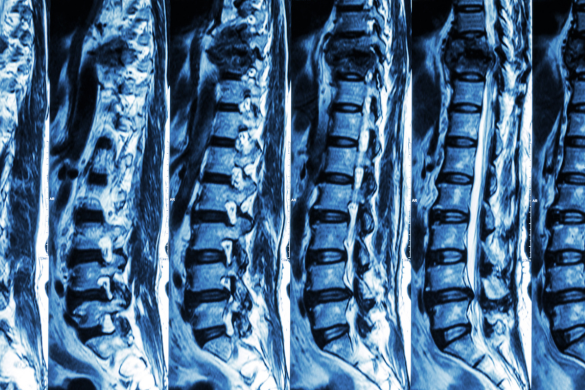

Understanding Spinal Cord Injuries

The spinal cord controls almost everything your body does — movement, balance, and even breathing. When that connection is damaged, the results can be severe. Some people experience numbness or weakness, while others lose complete control over parts of their body.